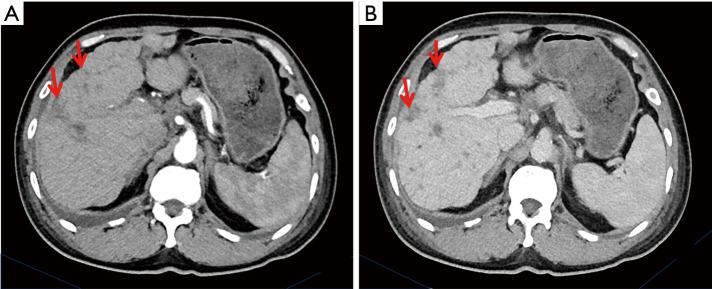

Case description: Here, we reported the genetic results of a patient with a PIK3CA gene mutation in scrotal Paget's disease who developed multiple metastases to the lymph nodes, liver, and bones during adjuvant radiotherapy, as well as the results of treatment with a PIK3CA inhibitor. The latest advances in this field were also summarized. The treatment response was evaluated as stable disease (SD) after 6 courses of docetaxel plus tegafur (DS regimen) chemotherapy. Then, a second-line treatment, a PIK3CA inhibitor, WX390, was administered with tolerable toxicity. There was a treatment-induced increase in blood glucose level during treatment, and insulin was administrated with good control. The progression-free survival (PFS) was 3.9 months and the overall survival (OS) was 16 months.